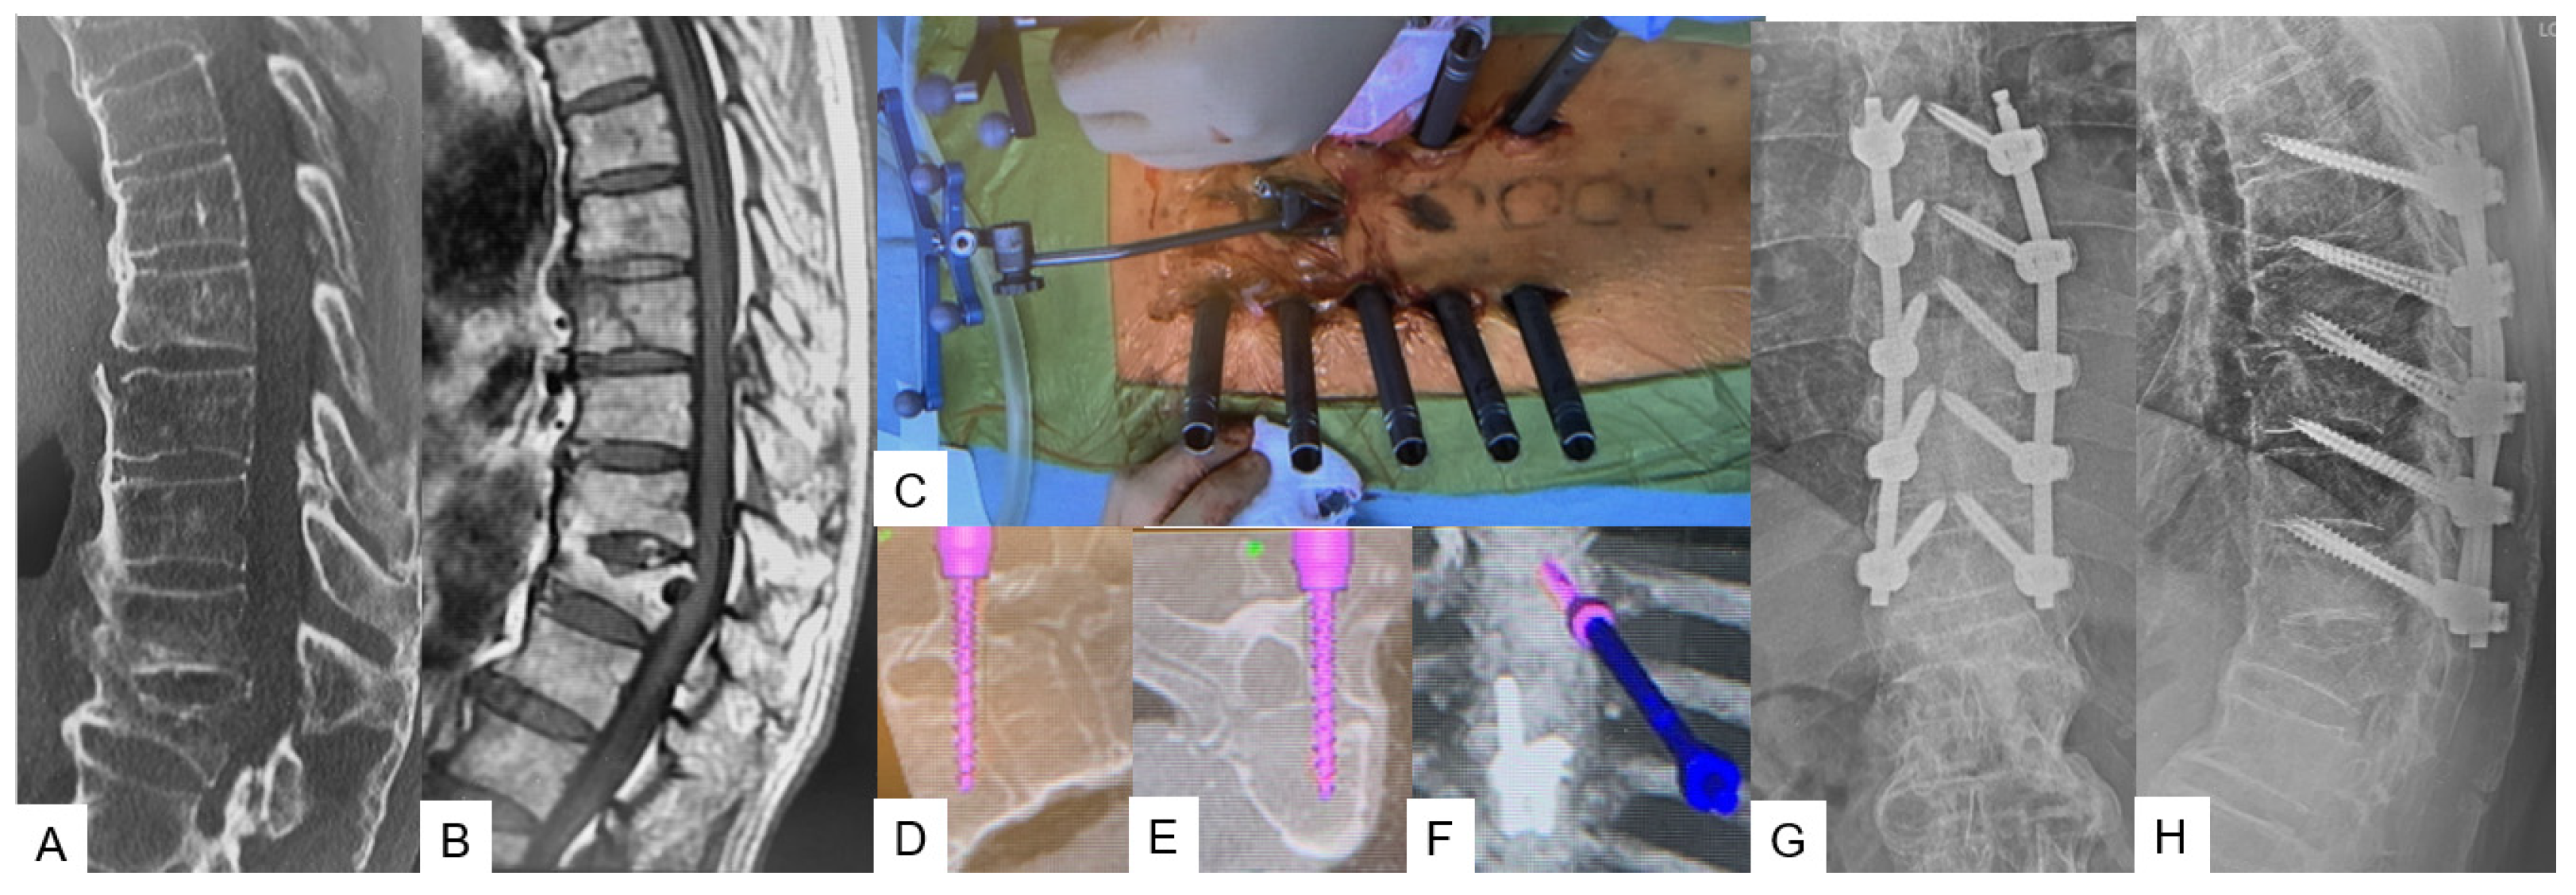

Transdiscal Screw for DISH (Diffuse Idiopathic Skeletal Hyperostosis) Fracture